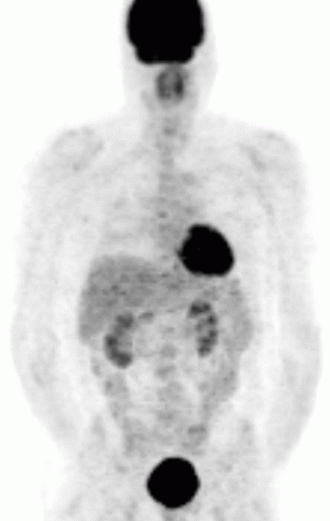

PET — Anterior Pancoast Tumor

FDG-PET showing intense uptake in an anterior Pancoast tumor (superior sulcus) of the lung

PET Downloaded 2026-03-15

Pet

Fdg

Wikimedia Commons: Anterior Pancoast tumor PET.jpg